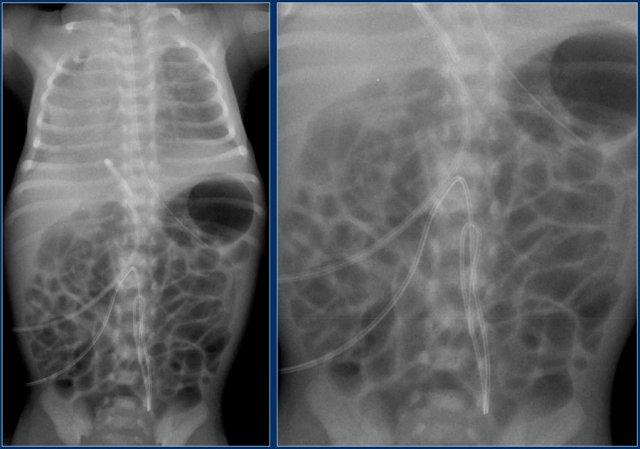

Đường truyền động mạch rốn (5)

Hãy quan sát kỹ hình ảnh trước.

Sau đó tiếp tục đọc.

Các phát hiện bao gồm:

- Đặt sai vị trí đường truyền động mạch rốn vào động mạch chậu trái.

- Đường truyền tĩnh mạch rốn ở vị trí quá sâu, đầu catheter nằm trong nhĩ phải.

- Ống thông dạ dày ở vị trí tốt.